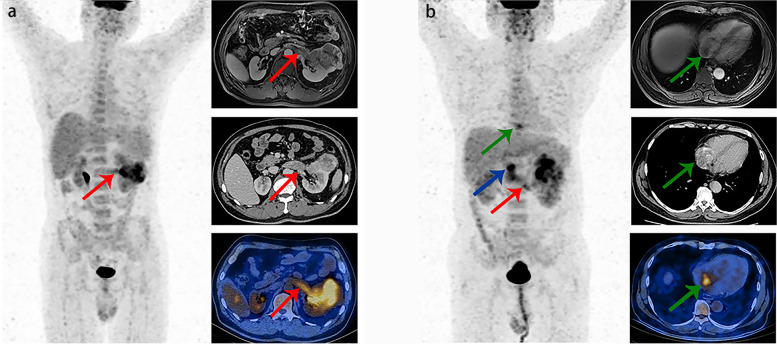

As shown in Table 3, the diagnostic value of 18F-FDG PET/CT imaging for the level of VTT (early VTT or advanced VTT) was further analyzed in 59 true-positive cases with VTT, including 49 early VTT and 10 advanced VTT. The sensitivity, specificity, accuracy, PPV, and NPV were 70.0, 100.0, 94.9, 100.0, and 94.2%, respectively. Kappa value between PET/CT and clinically confirmed results was 0.795 in diagnosing the level of VTT. The typical cases are shown in Fig. 2.

Fig. 2.

a Images in a 57-year-old male with ccRCC demonstrate left renal vein tumor thrombus (red arrows), with VTT SUVmax of 4.5 (left image: anterior maximum intensity projection image obtained at 18F-FDG PET; right upper image: axial contrast-enhanced MRI image; right middle image: axial contrast-enhanced CT image; right lower image: axial fused PET/CT image). b Images in a 55 year-old male with ccRCC demonstrate left renal vein tumor thrombus (red arrow), inferior vena cava tumor thrombus (blue arrow), and tumor thrombus in the right atrium (green arrows), with VTT SUVmax of 5.7 (left image: anterior maximum intensity projection image obtained at 18F-FDG PET; right upper image: axial contrast-enhanced MRI image; right middle image: axial contrast-enhanced CT image; right lower image: axial fused PET/CT image)